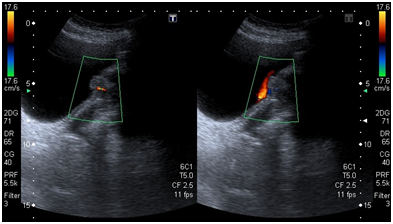

A 54-year old white woman, without significant past medical history other than menopause since 2years ago presented with post coital hematuria and also she had urinary tract infections (UTIs), documented by urine cultures (Proteus Mirabillis). No other associated symptoms. She received antibiotic therapy with quinolones. The urine cytology was negative. The assessment by the Gynecology service was normal. The renal ultrasound (US) Each kidney was normal, preserved cortico medullary differentiation and without dilated collecting systems. There was irregularity zone in the mucosa close to bladder neck, measuring 1x0.5cm. Cystoscopy revealed an edematous and erythematosus lesion of 1x1.5cm in the posterior wall of the bladder neck that extended into the urethra. In pelvic magnetic resonance imaging (MRI) a pelvic mass was evident measuring 35x38x47mm, widening the bladder neck at this level, nonspecific inguinal adenopathies and a left iliac node with malignancy aspect.

The pelvic examination during the transurethral resection of bladder (TURB) revealed a palpable nodule on the anterior wall of the vagina and there was not others remarkable findings. The pathology of transurethral resection of bladder confirmed urethra adenocarcinoma muscle-invasive with invasion of bladder neck. She was taken to an extension study (toracoabdominopelvic scan) in which the metastatic lesions were discarded (Figure 1-3).

Figure 1 Initial pelvic ultrasound.

Figure 2 Initial pelvic ultrasound.